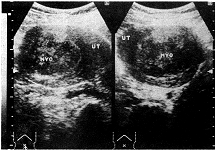

子宫肌瘤变性的声像图特点:(1)玻璃样变:病变切面失去旋涡状结构变为同质、其回声较为衰减(图1)。本组有3例占1.84%;(2)红色变性:为一种特殊型肌瘤坏死,常发生于较大的肌瘤中,妊娠期或产褥期易发生此种变性,切面呈肉红色、保持旋涡状外形,声像图上肿瘤明显衰减,界限不清(图2)。本组有5例占3.06%;(3)囊性变:当玻璃样变继续发展、液化形成许多大小不等的空腔,也可融合成一大囊腔,囊腔内壁光滑、囊内含液体多无色透明。前者有时很像葡萄胎,后者酷似卵巢囊肿,仔细观察瘤体的非囊区仍可见肌瘤的特点,回声较强,亦可以很弱或杂乱(图3,4)。本组有4例,占2.45%;(4)钙化:多发生于玻璃样变坏死后、由于肌瘤血液循环障碍、钙盐被组织成分及其他变性物质所吸收而沉积,超声图像显示为增强的回声团其后伴声影。本组有3例占1.84%。

图4 子宫平滑肌瘤伴囊性变(手术病理证实)